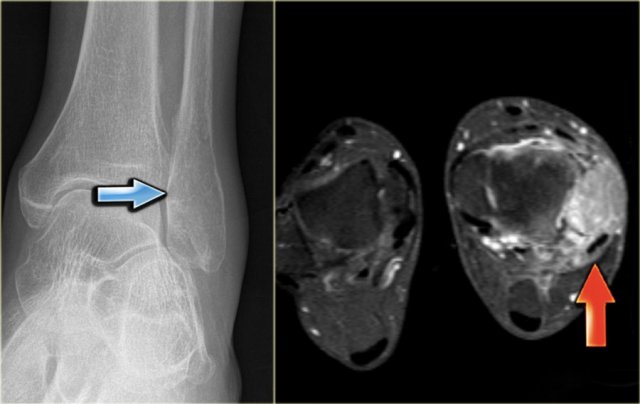

Here a patient with an eccentric lytic lesion in the metaphysis of the proximal fibula.

Coronal T1WI and T1WI with Gd and fatsat demonstrate the extension of the lesion on both sides of the physeal plate.

There is rim enhancement and edema in the bone marrow and soft tissues.

Brodie abscess

A Brodie abscess is a subacute osteomyelitis, which may persist for years before converting to a frank osteomyelitis. Brodie abscess present as an osteolytic bone defect with sharp borders surrounded by extensive reactive sclerosis.

The radiograph demonstrates an ill-defined osteolytic lesion in the tibia with extensive reactive sclerosis and solid periosteal reaction.

The T1WI+Gd+FS shows that the lesion extends through the physeal plate into the epiphysis.

There is a thick rim of enhancement and extensive reactive edema.

Final diagnosis: Brodies abscess.